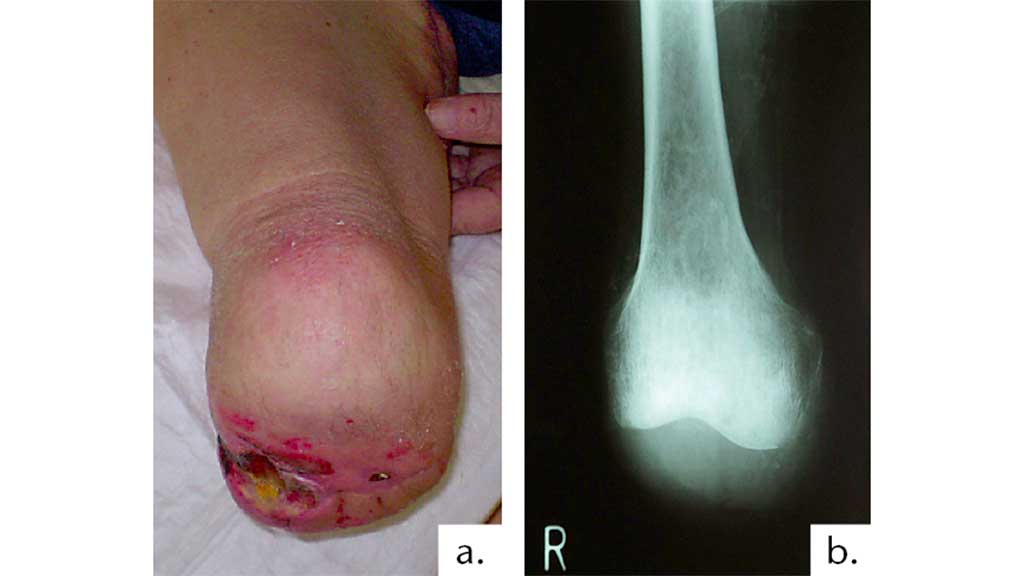

Legt der Chirurg die Wundnarbe in den Bereich der zukünftigen Belastungszone des Beines in der Knieexartikulationsprothese, führt dies zu einem großen Hindernis und einer Ablehnung des Gebrauchs der Prothese (Abb. 8).